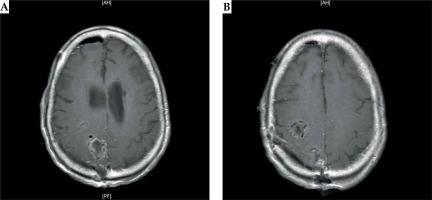

Post-operative MRI revealed the gross total resection of both right frontal and right parietal tumors. The last follow-up visit on October 27th, 2016 demonstrated the absence of tumor recurrence and no radiation necrosis (Figure 3). The patient excelled in the post-operative setting and had no neurological decline. Renal function precluded the patient from chemotherapy, and he remained disease-free for a significant period. His QoL was assessed before the procedure and at every follow-up, with questionnaires and mini-mental state examination (MMSE) as well as functional assessment of cancer therapy-brain (FACT-Br) questionnaire. The patient had an uneventful post-operative course and left a rehabilitation facility after 14 days. He developed a deep venous thrombosis (DVT) and subsequently a pulmonary embolism (PE), for which he was treated with anticoagulation. Eventually, the patient developed failure to thrive and was sent to a hospice, where he passed away one month later.

Fig. 3

A) Post-operative MRI of the brain after the right frontoparietal craniotomy demonstrating the intraoperative placement of 131Cs brachytherapy seeds: axial T1-weighted images demonstrate an anterior posterior right frontal cavity with 131Cs seeds. B) Post-operative MRI of the brain after the right frontoparietal craniotomy demonstrating the intraoperative placement of 131Cs brachytherapy seeds: axial T1-weighted images demonstrate right parietal cavity implanted with 131Cs seeds